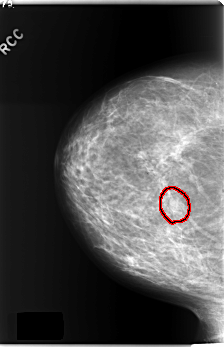

C_0240_1.RIGHT_CC

RIGHT_CC LINES 5896 PIXELS_PER_LINE 3800 BITS_PER_PIXEL 12 RESOLUTION 50 OVERLAY

FILE: C_0240_1.RIGHT_CC.OVERLAY

TOTAL_ABNORMALITIES 1

ABNORMALITY 1

LESION_TYPE MASS SHAPE OVAL MARGINS ILL_DEFINED

ASSESSMENT 4

SUBTLETY 3

PATHOLOGY BENIGN

TOTAL_OUTLINES 1

BOUNDARY